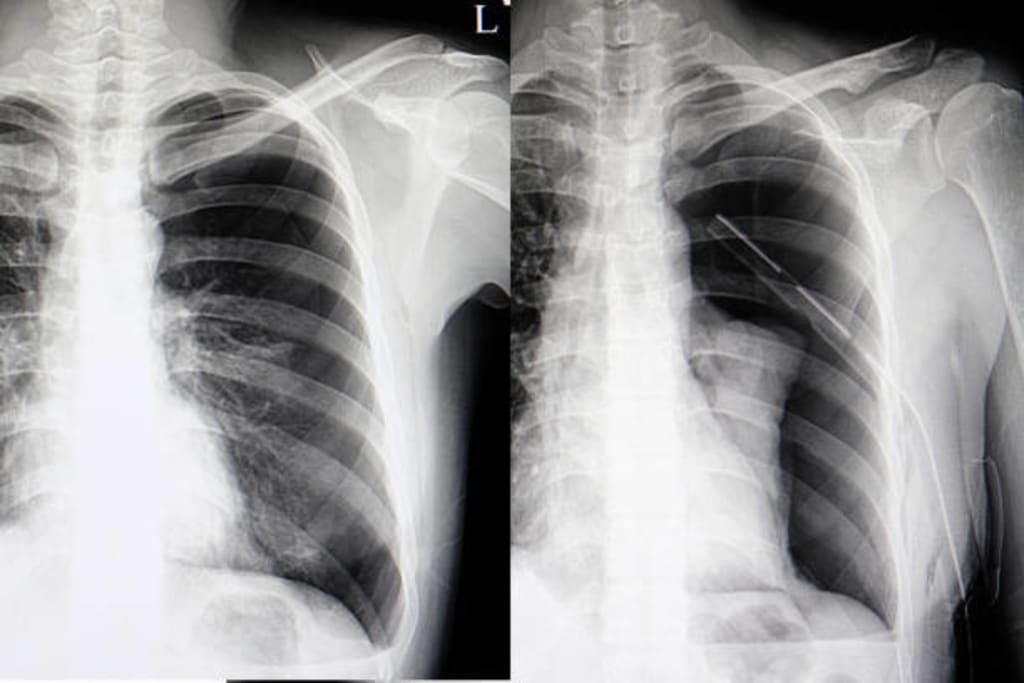

Tension Pneumothorax And Hemothorax

Two significant medical diseases that can damage the lungs and make breathing difficult are tension pneumothorax and hemothorax.

When air builds up in the pleural space, which is the region between the lung and the chest wall, tension pneumothorax results, which raises pressure inside the chest cavity. If neglected, this can result in a collapsed lung, compression of the heart and main blood arteries, and even death.

Contrarily, a hemothorax is a collection of blood in the pleural space that can also result in a collapsed lung and respiratory problems. It might be brought on by trauma or bleeding issues.